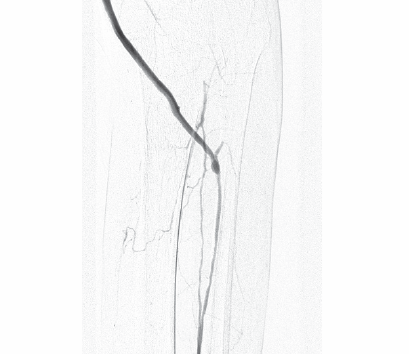

Выделение передней большеберцовой артерии предложенным нами способом позволяет избежать дополнительного хирургического доступа и снизить травматичность операции в целом. Кроме того, применение предложенного доступа позволяет расположить кондуит вдоль сосудистого пучка без перегибов, что особенно актуально при использовании синтетических сосудистых протезов (рис. 4).

![screenshot_36]()

Рисунок 4. Ангиография после аутовенозного шунтирования по методике «in situ» в переднюю большеберцовую артерию

Зачастую, ввиду выраженного стено-окклюзирующего процесса, данные артерии не контрастируются при ангиографии даже при условии из проходимости. Таким образом, предлагаемый нами способ выделения передней большеберцовой артерии обеспечивает возможность ревизии всех артерий голени из одного хирургического доступа, что позволяет выполнить реваскуляризацию нескольких артерий, тем самым улучшить прогноз лечения.